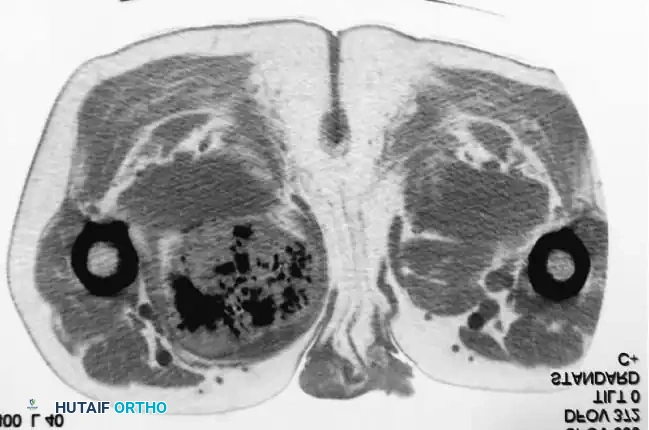

Intraoperative Imaging and Margin Assessment

Continuous intraoperative assessment using fluoroscopy and frozen section pathology is mandatory. The following images demonstrate various stages of complex upper extremity resections, allograft preparations, and prosthetic implantations across the humerus and elbow joint.

Distal Humerus and Elbow Reconstruction

When tumors involve the distal humerus, resection often requires sacrifice of the collateral ligaments and the articular surface of the elbow. Reconstruction is typically achieved using a linked, semi-constrained total elbow arthroplasty designed for oncologic defects.